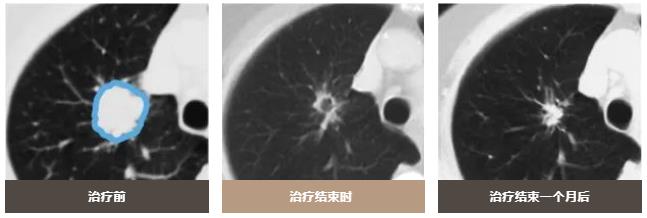

质子治疗可以减少对周围正常肺组织的照射剂量,只对病变部位进行集中照射。

治疗效果